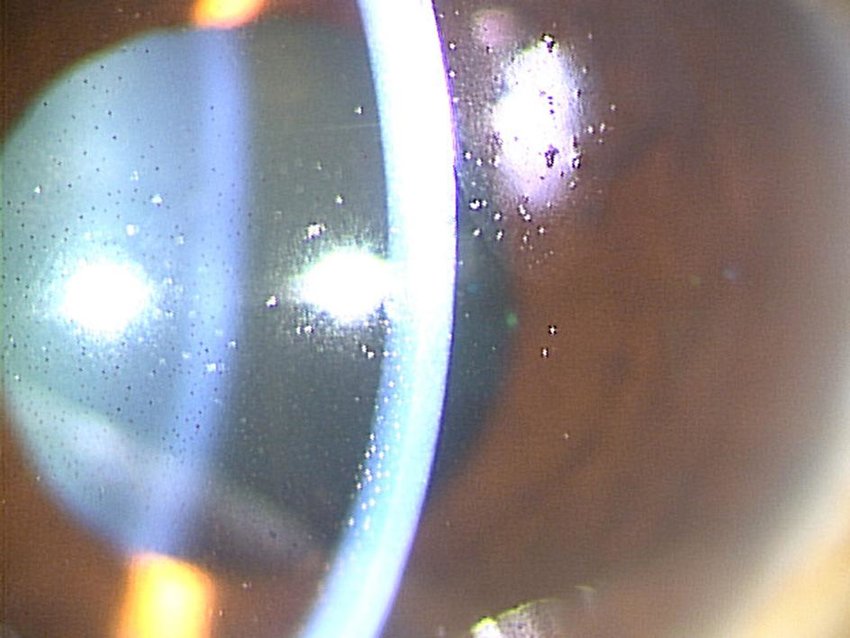

<포도막염, 전방출혈>

어떤수술이나 마찬가지로,

녹내장 섬유주절제술 이후에도 수술이후 안구내에 염증이 발생합니다.

술후 모든 환자들에서 경미한 포도막염 소견이 관찰되고,

스테로이드 점안제(topical steroid 안약)와 산동-조절마비제(cycloplegics)로 치료할수 있습니다.

전방출혈의 경우 머리를 높게하고 안정시키는 보조요법정도만으로도 치료되는 경우가 대부분입니다.

공막 누공을 만들 때 그 위치를 scleral spur (공막극) 보다 뒤쪽으로 만들 때 발생가능성이 높아집니다.